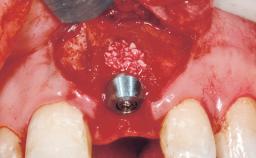

A 39-year-old male patient presented with a chief complaint of discomfort and gingival discoloration around his maxillary left central incisor. He was in good general health and was a non-smoker. His past dental history was significant because of the traumatic fracture of tooth 21 in a sporting accident at age 13. Initial dental treatment included endodontic therapy and a full-coverage restoration. The patient became symptomatic 5 years later, when structural failure of the tooth resulted in the dislodgment of the crown. Endodontic retreatment, apical surgery, and post-and-core restoration were performed.

Placement Protocol Early or late implant placement

Bone Volume Deficient horizontally, requiring prior grafting

Bone Augmentation Horizontal|Staged

Augmentation Materials Xenogenous|Membrane